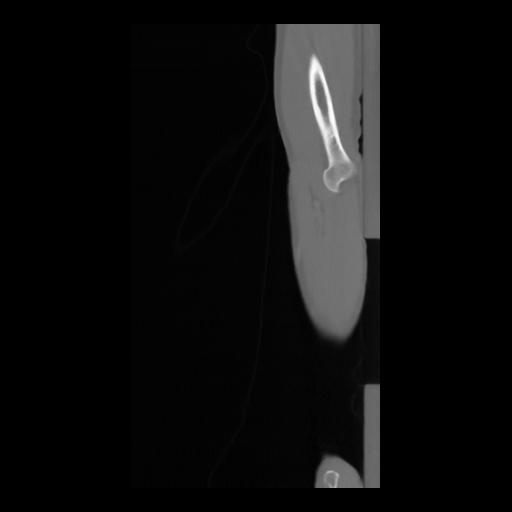

36 CUERPO,CE,Sagittal,3.000,CUERPO,Sagittal,